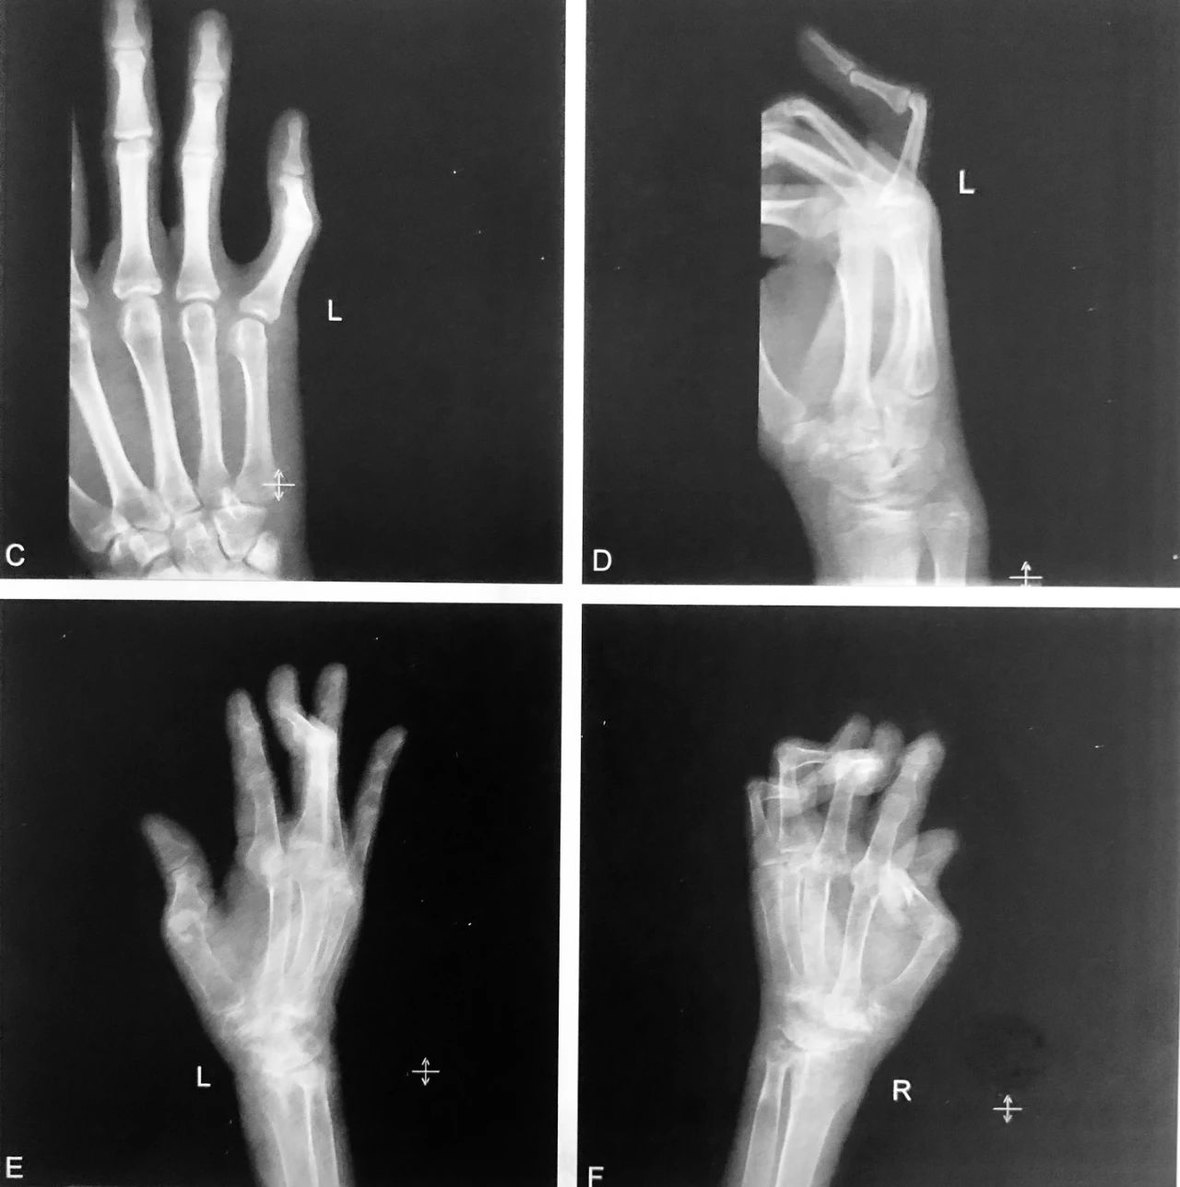

鹅 颈 畸 形

分别为干眼症患者,外伤患者,类风湿性关节炎患者的鹅颈畸形

判读要点:

1、先天性手指鹅颈畸形罕见;后天多种疾患均可导致鹅颈畸形,以外伤和类风湿性关节炎最常见;

2、在手掌 x 线侧位或斜位片、CT 或 MRI 矢状位显示;

3、表现为近侧指间关节过伸,而远端指间关节屈曲。